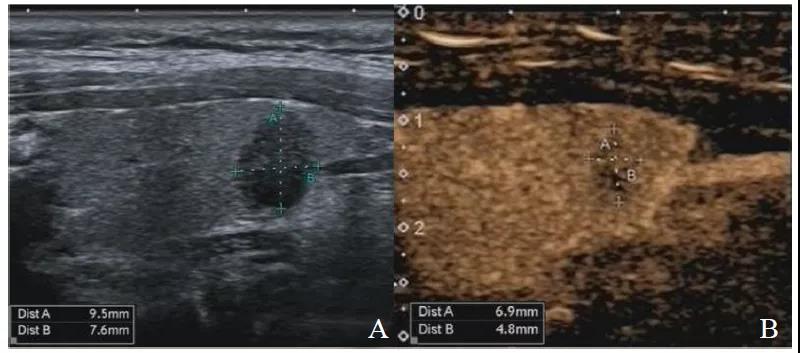

图1显示PTMC组结节大小的CEUS测值小于灰阶超声测值,图2显示良性组结节大小的CEUS测值与灰阶超声测量相近。表2显示PTMC组结节大小的CEUS测值明显小于灰阶超声测值(P<0.05)、良性组结节大小的CEUS测值与灰阶超声测值差异无统计学意义(P>0.05)。

图1 PTMC组结节大小测量

注:CEUS测量小于灰阶超声测值。A为灰阶超声图像;B为CEUS图像。